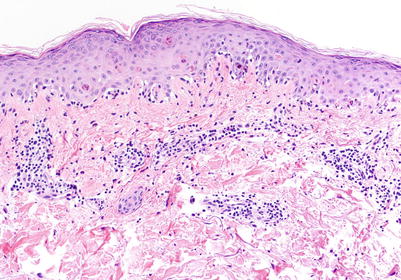

Fig. 5.2

Interface dermatitis with necrotic keratinocytes at and above the epidermal basal layer, corresponding to aGVHD histologic grade II (H&E, 100× magnification)